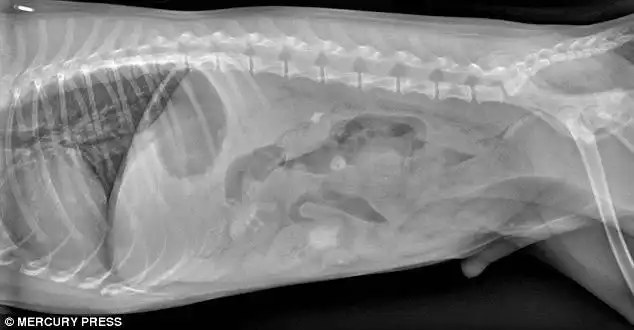

Лабрадор, проглотивший 3 массивных рыболовных грузила